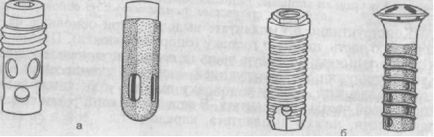

Ábra. 278. subperiosteal implantátumokat.

és - keretében egyoldalú subperiosteal implantátum a modellt; b - a bilaterális subperiosteal implantátum modell szerint.

2. Subperiosteal implantátumok (subperiosteal) fém keretek ötvözetből nemesfém ötvözetek vagy rozsdamentes acél. Anyaguk alapján egyedileg anatómiai leadott lövés skeletonized alveoláris rész. A telepítés után az illeszkedés és a fedél kerettel helyet előre az elválasztott mucoperiosteal szárnyak és varrt. Keresztül a csappantyú a szájüregben a fém csapok, amely szolgálhat a támogatása rögzített hidak vagy kiegészítő tartóelemek számára kivehető fogsor. Ezeket fel lehet használni mind a felső és az alsó állkapocs, de a legtöbb esetben alkalmazott subperiosteal implantátumok a mandibula (ábra. 278).